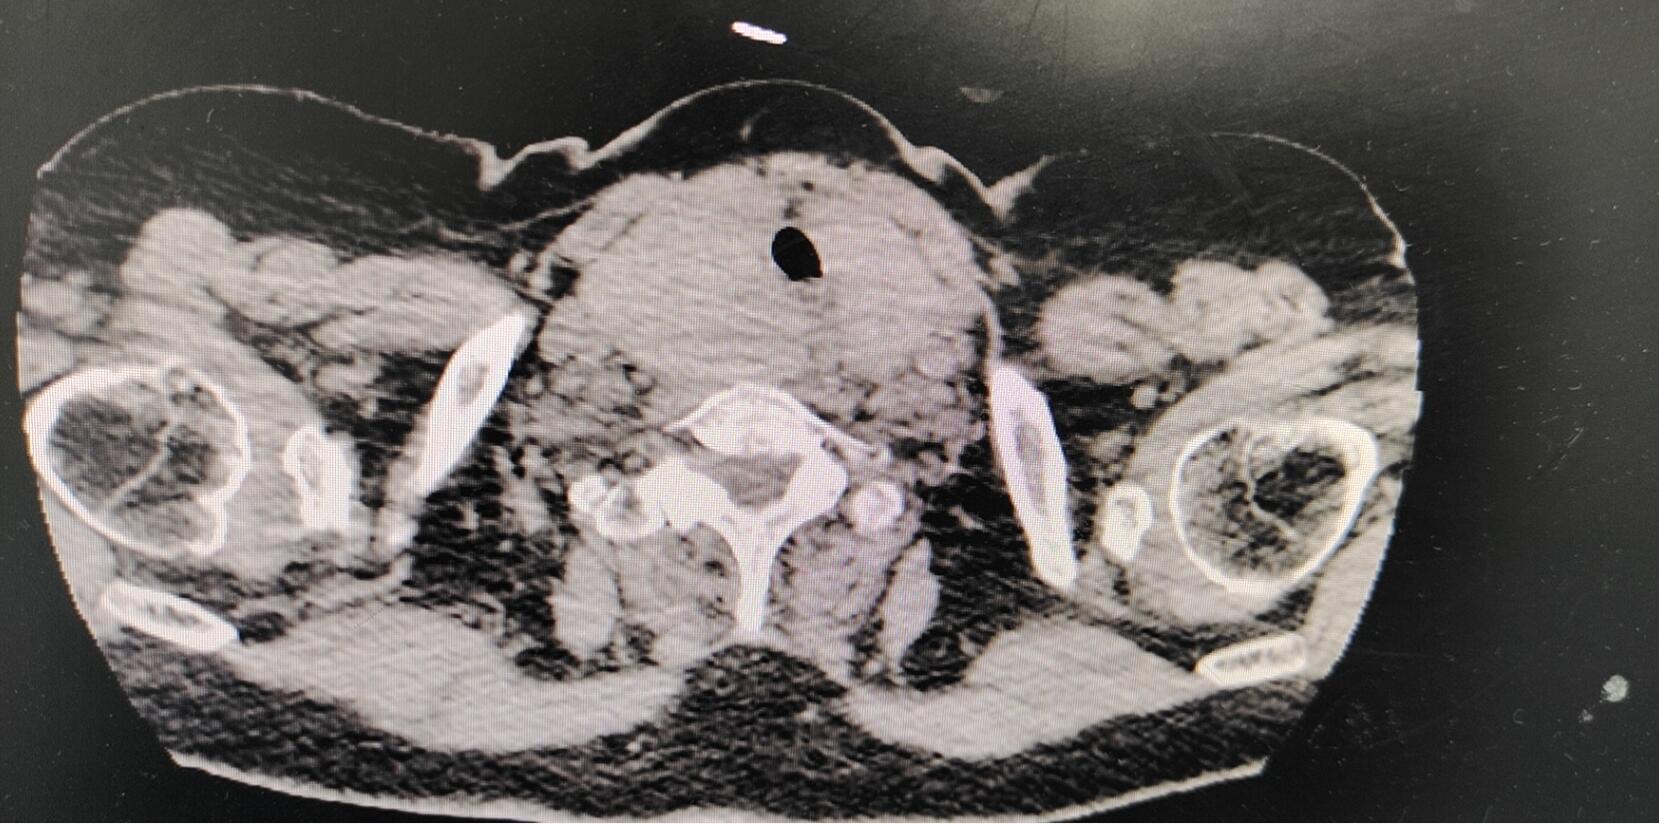

CT影像

80岁高龄的张女士,因“颈部鹅蛋样大小肿物,伴有疼痛及呼吸困难”导致气管受压、变形,夜间入睡憋醒,十分痛苦。一家人心急如焚,曾去往多家上级医院咨询问诊,均因老人年事已高,肿物较大且既往有高血压、糖尿病、心脏病、脑梗塞等多种病史,完整切除肿瘤的可能性极小,而拒绝为其手术。残酷的现实一次次迎面击来,却从未打消这一家人为老人治病的诚心。

辗转求医苦无果,柳暗花明幸有你。终于1月25日,患者一家几经周折,慕名找到了我院普外一科李增德主任及两腺外科学科带头人宋希福主治医师。听了患者一家的讲述,科室人员深受触动,并答应竭尽全力为老人治病。李主任带领两腺外科学组反复研究患者资料,考虑虽然患者肿瘤较大,但仍有手术机会。宋医生仔细为老人查体,经过一系列检查考虑“甲状腺 占位 CA?”,并第一时间向老人家属说明手术的必要性及风险性。经家属商议后,决定同意为老人手术治疗。